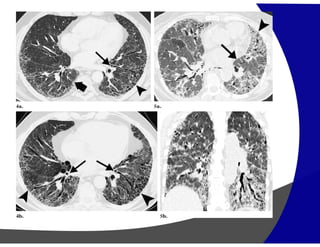

Nodulos centrolobulares

Pneumoconiose do trabalhador de carvao

Nódulos centrilobulares

(Pneumonia de Hipersensibilidade)

Arvore em brotamento

Disseminação endobrônquica

Nodulos perilinfaticos

Sarcoidose

Nodulos aleatorios

Tuberculose miliar

Padrão nodular Distribuição Centrolobular • Pneumoniade Hipersensibilidade • Bronquiolite • Disseminação endobronquica Peri-linfatica • Sarcoidose • Silicose • Linfangite Aleatória • Metastases (hematogênicas) • TB miliar